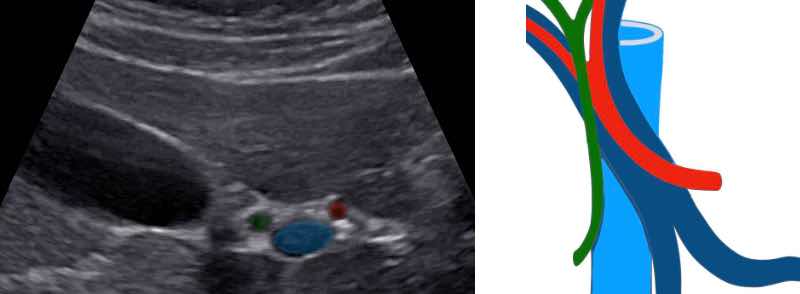

Tronc porte avec flux hépatopète et veines sus-hépatiques hépatofuges.

Tronc porte et branches portales hépatopètes.

Vitesse maximale dans le tronc porte : cm/s.